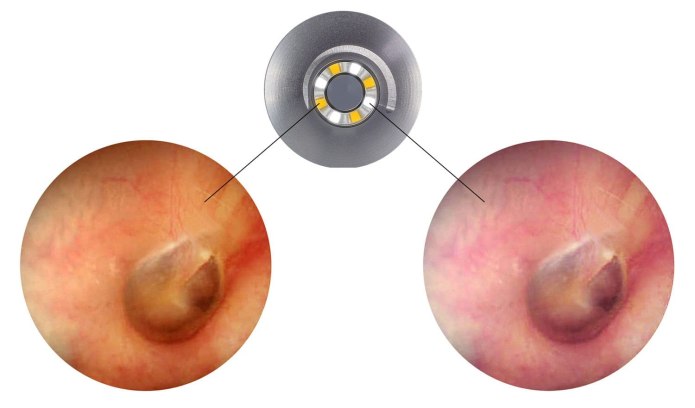

Dwa kolory oświetlenia 2×4 diody LED - 3000K i 6000K. Przełączanie dzięki jednemu przyciskowi. Po 3 minutach otoskop Luxamed Auris LED zoastaje automatyczne wyłączony (oszczędność energii). Żywotność diod LED stanowi około 100 000 godzin.

Światło białe ciepłe jest podobne do standardowych żarówek żarnikowych, co stanowi optymalne oświetlenie w trakcie badanie otoskopowego.

Generowane światło przez otoskop Luxamed jest poprzez diody ulokowane na części zewnętrznej główki optycznej, przy miejscu założenia wziernika. Powoduje to, że transmisja światła nie jest zachwiana i płynie we właściwe miejsce. Nie dochodzi do braku ograniczenia pola widzenia.